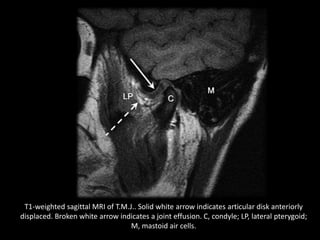

T1-weighted sagittal MRI of T.M.J.. Solid white arrow indicates articular disk anteriorly

displaced. Broken white arrow indicates a joint effusion. C, condyle; LP, lateral pterygoid;

M, mastoid air cells.

T2-weighted sagittal view of T.M.J.. Solid white arrow indicates articular disk anteriorly

T1-weighted sagittal MRIof T.M.J.. Solid white arrow indicates articular disk anteriorly displaced. Broken white arrow indicates a joint effusion. C, condyle; LP, lateral pterygoid; M, mastoid air cells.

• 99.

T2-weighted sagittal viewof T.M.J.. Solid white arrow indicates articular disk anteriorly displaced. Broken white arrow indicates a joint effusion. C, condyle; LP, lateral pterygoid; M, mastoid air cells.